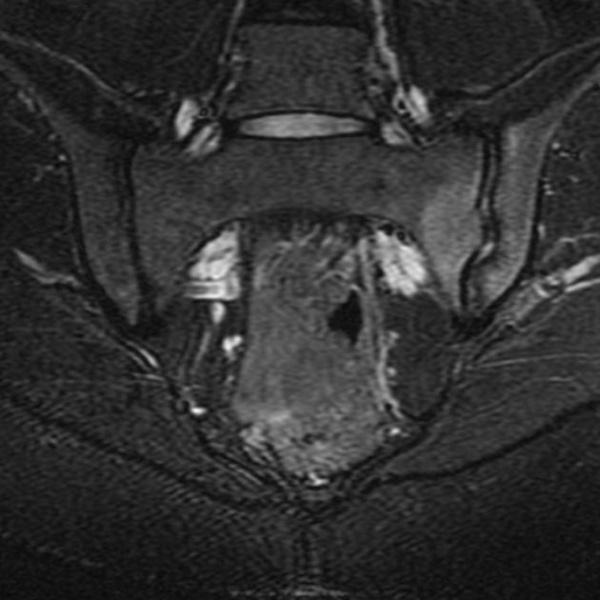

Kết quả chụp cộng hưởng từ cho thấy mức độ tổn thương của khớp cùng chậu, cơ, dây chằng, vết nứt gãy nhỏ tại khớp. Với phương pháp này, bác sĩ có thể chẩn đoán mức độ viêm của khớp cùng chậu từ giai đoạn khởi phát mà chụp X Quang và CT không phát hiện được.